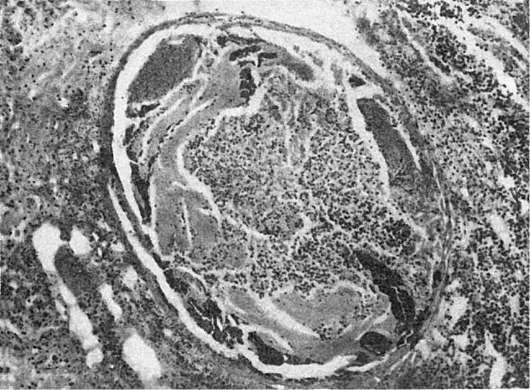

Рис.

282. Острый септический полипозно-язвенный эндокардит

при вовлечении в процесс легочных вен (тромбофлебит легочных вен) гнойники появляются в органах системы большого круга кровообращения - в печени (абсцессы печени), почках (гнойничковый нефрит), подкожной клетчатке, костном мозге (гнойный остеомиелит), в синовиальных оболочках (гнойный артрит), клапанах сердца (острый септический полипозноязвенный эндокардит, см. рис. 282). Гнойники могут распространяться на соседние ткани. Например, при абсцессе легкого развиваются гнойный плеврит и перикардит, при метастатическом абсцессе печени - гнойный перитонит; гнойники почки осложняются пери- и паранефритом, гнойники кожи - флегмоной и т.д. Гиперпластические процессы в лимфатической (иммунокомпетентной) и кроветворной тканях выражены слабее, чем при септицемии. Поэтому лимфатические узлы резко не увеличиваются, однако селезенка может быть типично септической, причем в пульпе ее обнаруживается большое число лейкоцитов (септический лейкоцитоз селезенки). В костном мозге омоложение его клеточного состава встречается редко. Межуточные воспалительные реакции в паренхиматозных органах весьма умеренны или отсутствуют.

Основные изменения касаются клапанов сердца. Преобладает изолированный эндокардит, который, по данным вскрытий, встречается в 6075% случаев. В 50% случаев поражаются только аортальные клапаны, в 10-15% - митральный клапан, в 25-30% - аортальный и митральный клапаны, в 5% - другие клапаны. Следовательно, септический эндокардит очень часто (в 75-80%) развивается на аортальных клапанах. Как на склерозированных, так и на несклерозированных клапанах возникает полипозно-язвенный эндокардит (рис. 284). При этом обычно на склерозированных клапанах появляются обширные тромботические наложения в виде полипов, которые легко крошатся и рано пропитываются известью, что весьма характерно для этого заболевания. После удаления

этих наложений обнаруживаются язвенные дефекты в склерозированных и деформированных створках клапанов, иногда поверхностные, иногда с нарушением целости клапана, образованием острых аневризм створок или массивным их разрушением. Тромботические наложения располагаются не только на створках, но и на пристеночном эндокарде, а при поражении аортальных клапанов распространяются на интиму аорты.